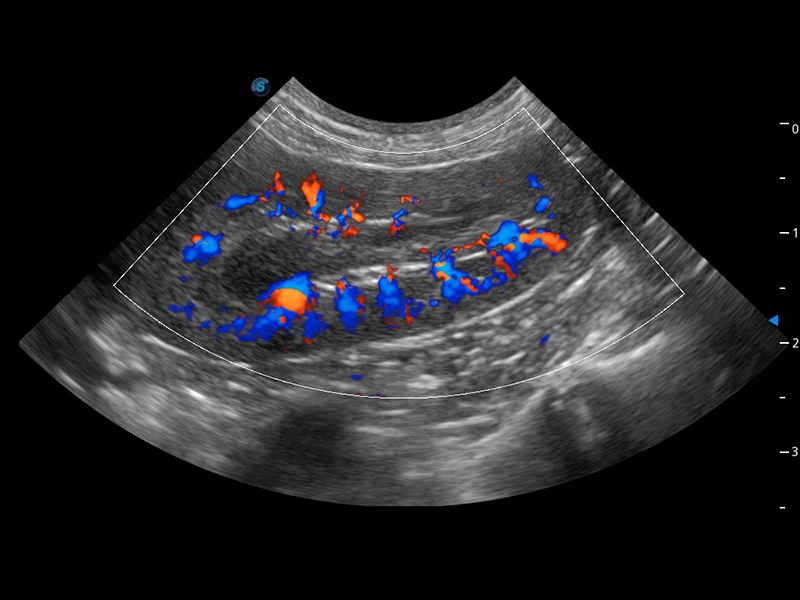

(犬)肾脏血流